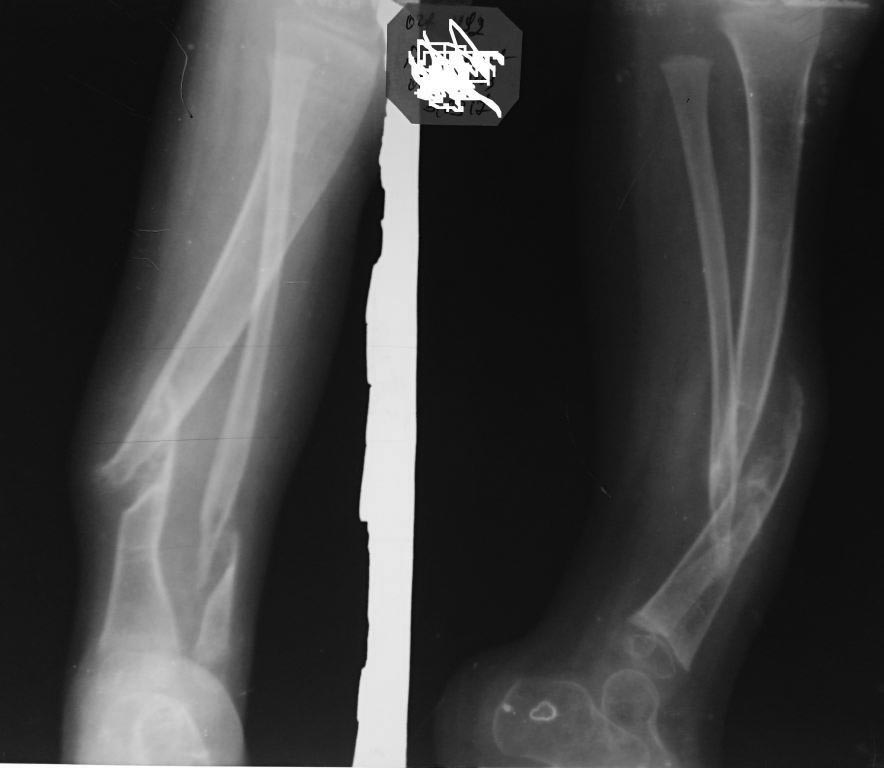

[Ortho] Врожденный ложный сустав костей голени

Пример будующего пациента

Имя     : pseudoarthrosis.jpg